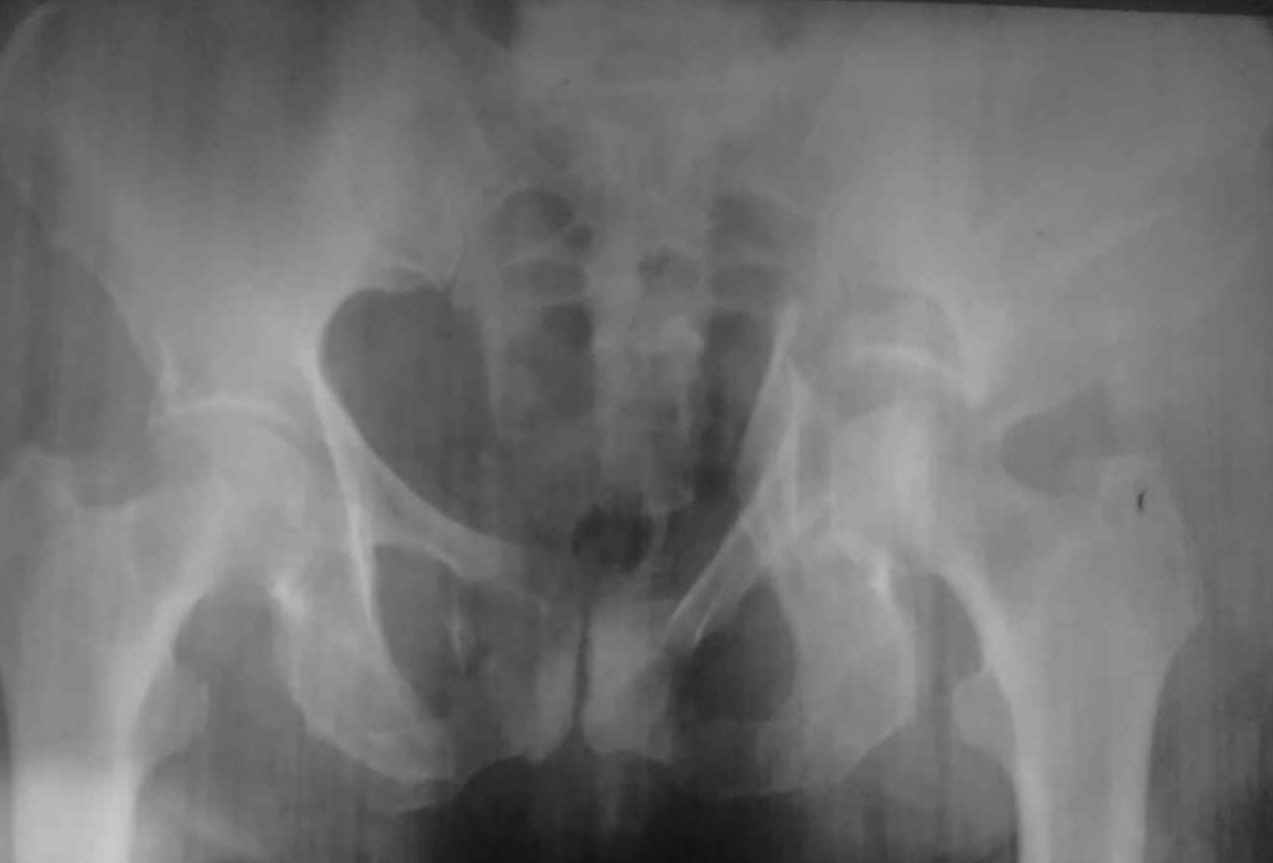

Множестевенный перелом костей таза с нарушением тазового кольца и вертлужной впадины слева с центральным вывихом бедра.

В <Межрегиональный Центр таза>. Больная 1941 года рождения поступила 30 апреля с дорожной травмы (была сбита машиной) с DS: Множестевенный перелом костей таза с нарушением тазового кольца и вертлужной впадины слева с центральным вывихом бедра. Оскольчатый перелом головки и хирургической шейки левого плеча без смещения. Была госпитализирована в ПИТ РАО, где находится по настоящее время. Проводилась противошоковая терапия, гемотрансфузия. После стабилизации состояния 01/05 наложена система скелетного вытяжения за мыщелки бедра. Предваряя Ваш вопрос о входящей проекции - она будет завтра. Могут ли родственники подъехать со снимками для консультации на предмет перевода в УНИИТО для дальнейшего лечения.